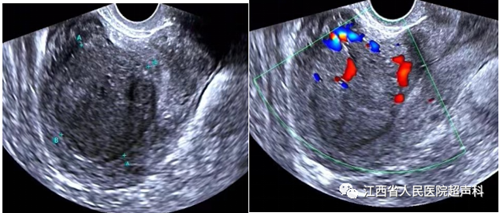

超声检查是公认的首选检查,能准确的观察到子宫的大小、形态,肌瘤的有无。MRI检查能发现直径0.3 cm的肌瘤,对于肌瘤的大小、数量及位置能准确辨别,是超声检查的重要补充手段。经阴道超声检查最常用。但对超出盆腔的肿物、肥胖及无性生活女性适用传统的经腹壁超声检查。

超声引导下微波消融术是利用微波的局部致热效应,在短时间内使针型辐射器周围的组织温度升高至可以使组织细胞蛋白质发生凝固性坏死的高温,造成组织细胞不可逆性凝固坏死,实现在保留子宫基础上达到子宫肌瘤组织和细胞原位灭活、肌瘤缩小或经自然腔道排出体外完全消失的治疗目的。

江西省人民医院超声医学科冯莉莉主任带领的团队从事微波消融已有8年经验,微波消融术的应用,使患者在灭活子宫肌瘤的基础上保留了子宫和生育能力,为广大年轻女性患者带来了福音,欢迎广大患者朋友前来咨询。